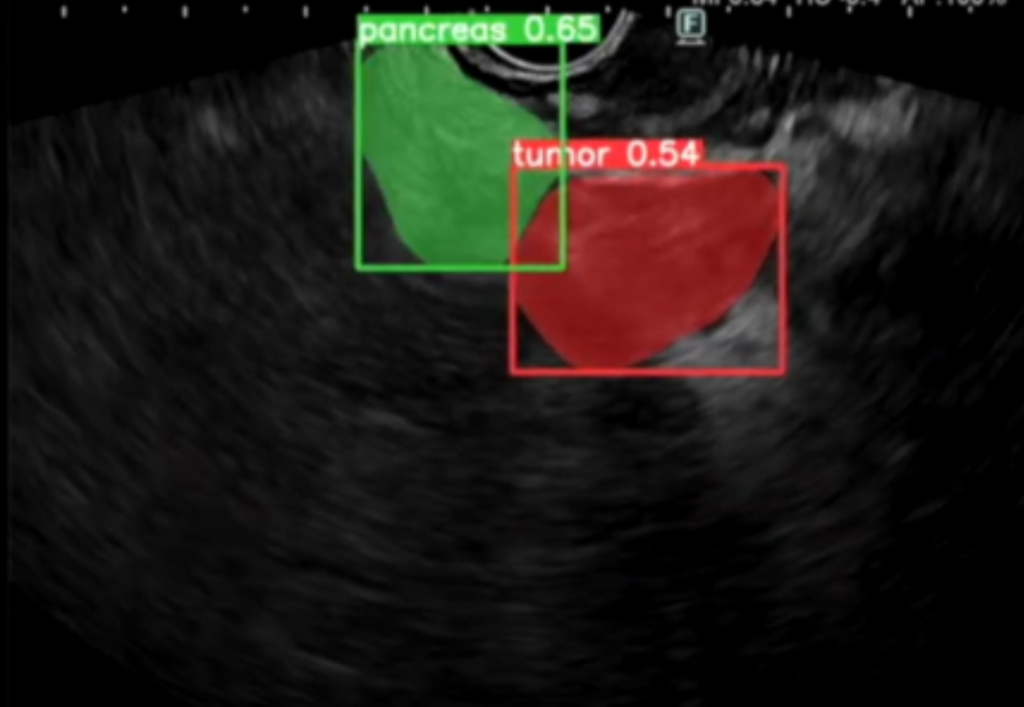

Precise labeling of anatomical features in endoscopic ultrasound helps build diagnostic tools for GI and oncology use cases.

Advanced surgical video labeling for AI-assisted procedures. We annotate surgical instruments, anatomical landmarks, tissue types, and procedural steps in endoscopic and robotic surgery footage, helping develop intelligent systems that enhance surgical precision and safety.